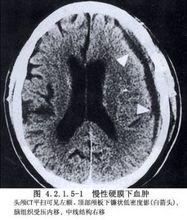

過去多認為慢性硬腦膜下血腫的形成是由於包膜血管的血漿滲入,增加了囊內滲透壓,致使血腫的體積不斷擴大。近年的研究表明,其形成的機制是因血腫包膜的外層內微血管不斷破裂出血和過度纖維蛋白溶解促進出血,使血腫體積逐漸擴大。因此,在治療上除了將囊內液體排空外,還需套用生理鹽水反覆沖洗的方法將局部的纖溶物質及纖維蛋白降解產物儘可能地沖洗掉,然後進行引流。行骨瓣開顱將血腫連同囊壁一併切除的手術方法,現已不作為首選,僅在囊壁異常增厚或已鈣化,鑽孔沖洗引流術難以使受壓的腦部回復時方始採用。(圖4.2.1.5-1)